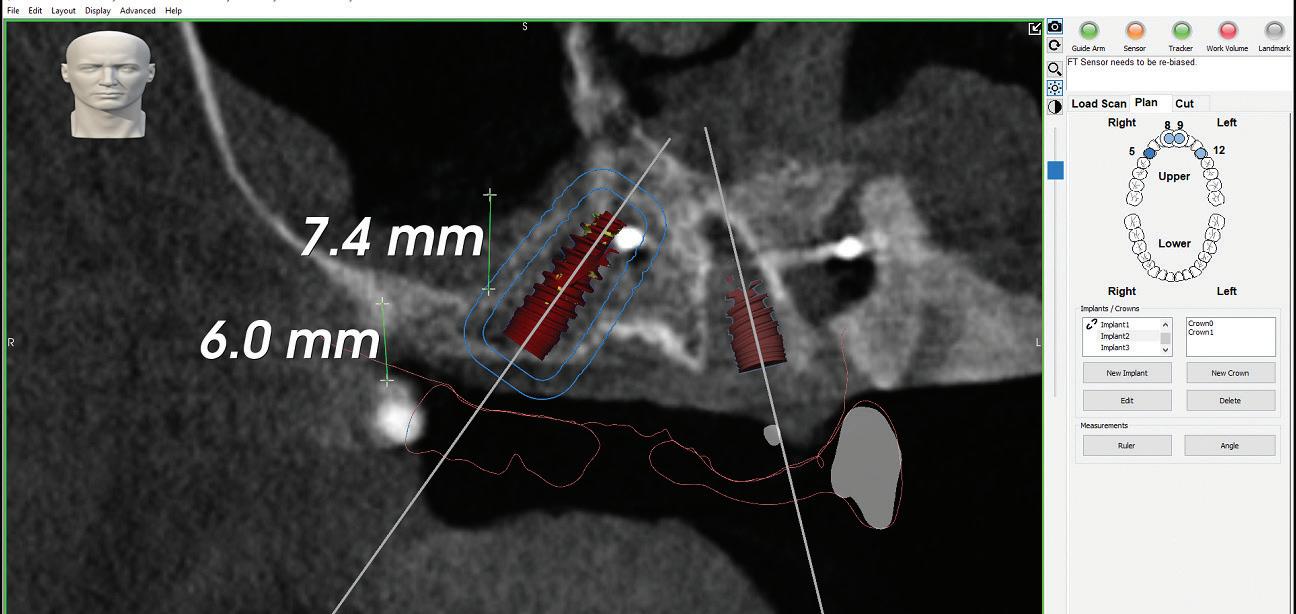

PROSTHETICALLY DRIVEN PLANNING

Tehnologia digitală redefinește terapiile implantare

• Chirurgia implantară cu cea mai inteligentă planificare și mai precisă execuție va necesita în continuare un finisaj protetic care funcționează biomecanic și realizează o estetică naturală ideală individuală. Dacă există un aspect al tratamentului protetic cu provocări în era digitală, acesta ar consta în munca artistică minuțioasă a ceramistului, cu modelarea și pictarea dinților pentru a imita natura.

Colaborarea profesională și planificarea ghidată protetic sunt esențiale pentru rezultate predictibile de succes.